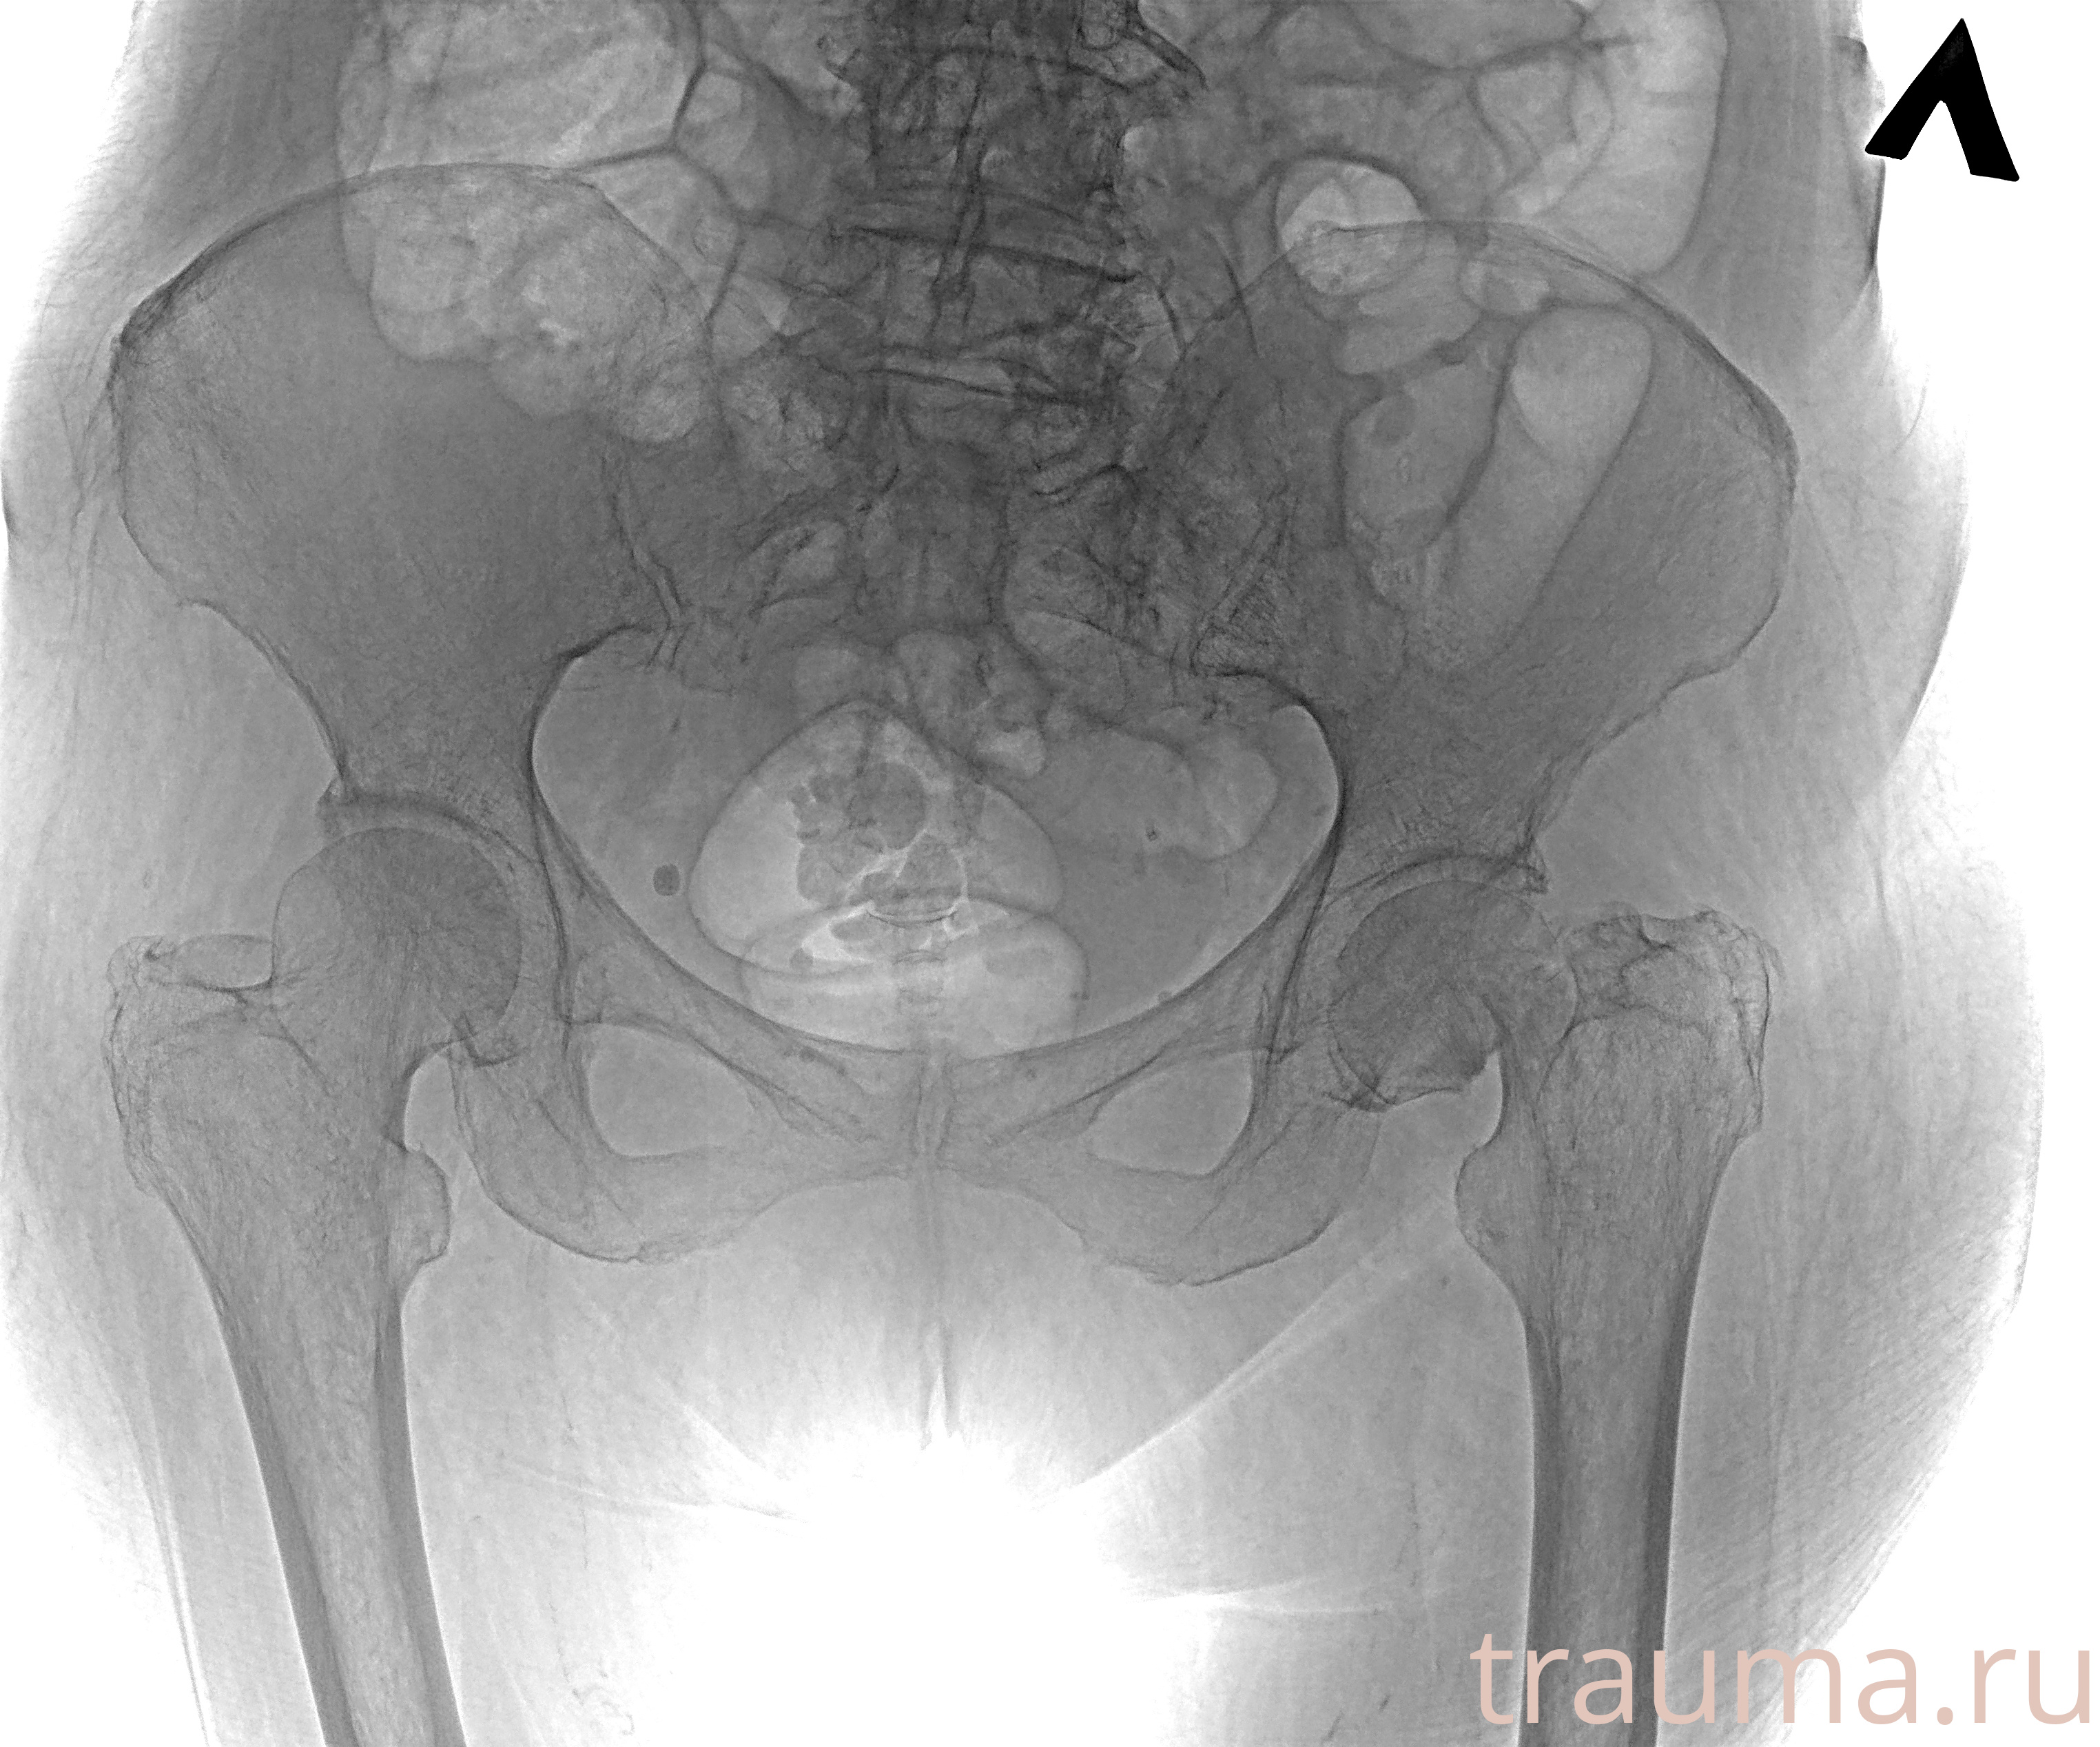

Рентген на дому: по вашему адресу приезжает врач-рентгенолог, травматолог-ортопед с мобильным рентгеновским аппаратом, проводит диагностику травмы или заболевания, делает необходимые рентгенограммы, дает рекомендации по дальнейшему лечению. Получить качественные снимки в домашних условиях возможно благодаря уникальной методике, разработанной МосРентген Центром для института  Склифосовского